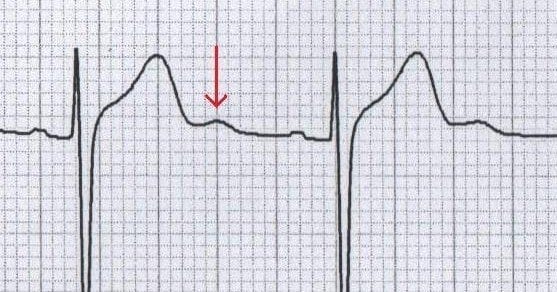

ECG Example – U Wave

Note that there is a positive deflection (arrowed) after the T wave, and before the next P wave, that is the U wave.

© Life in the Fast Lane. Licensed under CC BY-NC 4.0